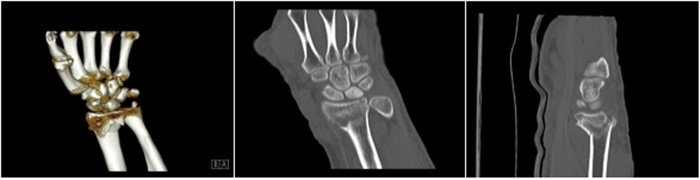

明峰CT搭載了領(lǐng)先的硬件技術(shù)平臺及系統(tǒng),強大的掃描能力可滿足臨床的各種要求,呈現(xiàn)更極致的細節(jié),為各臨床科室提供高品質(zhì)的圖像。薄層掃描,消除部分容積效應,提高各向同性。配合高分辨率算法,有助于細微結(jié)構(gòu)和形態(tài)學顯示。